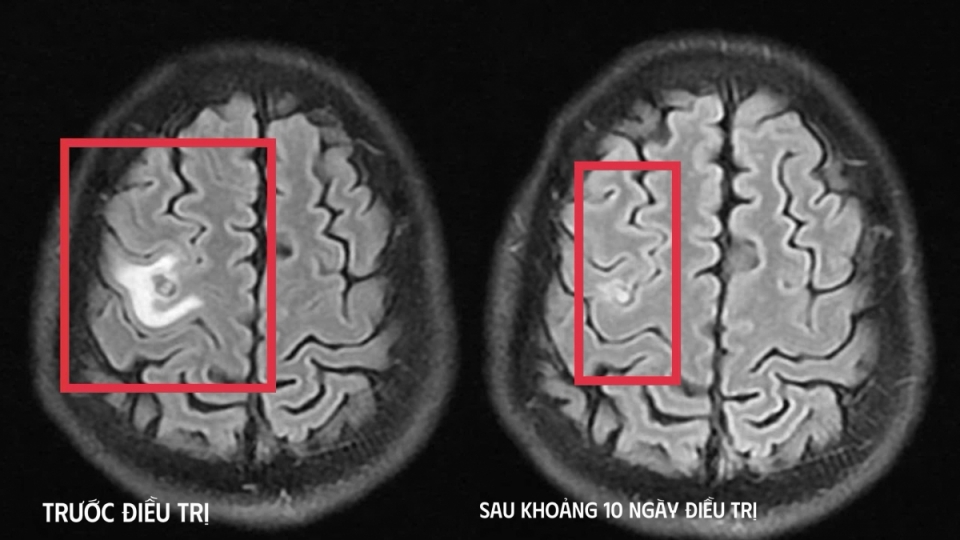

VOV.VN - Bệnh nhân nhập viện trong tình trạng co giật, đau đầu – những biểu hiện dễ khiến nhiều người nghĩ đến u não, song kết quả chụp cộng hưởng từ (MRI) sọ não cho thấy bị tổn thương não do ký sinh trùng.